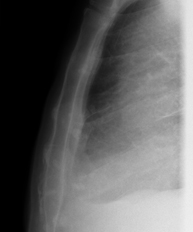

- Tórax

- RX Tórax

Técnica mediante la cual, utilizando rayos X, se obtienen imágenes de la caja torácica (corazón, pulmones, arcos costales, clavículas, etc.) para su estudio.

Una radiografía de tórax es una técnica mediante la cual, utilizando una pequeña dosis de radiación, se obtiene una imagen bidimensional de la caja torácica y su contenido (pulmones, corazón, mediastino, etc.). Es una de las pruebas médicas más comúnmente realizadas.